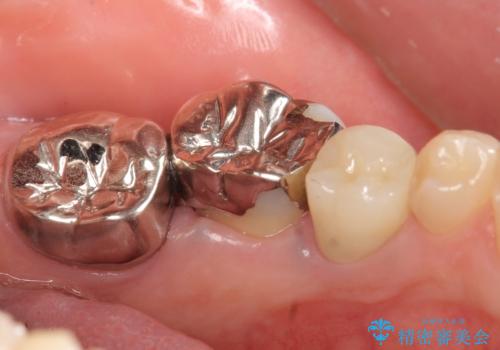

- 左下の奥歯がズキズキ痛むので診て欲しいといらっしゃった方の症例です。他院では5番目と7番目の歯を抜歯してインプラントと言われたが、出来れば歯を残したいとのことでした。

痛みの原因は6番目の虫歯であること、5番目、6番目の歯は歯茎より深い虫歯であり現状では保存が難しいことを説明した上で、歯を挺出させる部分矯正と歯茎を下げる歯周外科を行いました。

虫歯が進み歯茎より深くなってしまうと、虫歯を取り残してしまうリスク、樹脂の硬化の妨げ、補綴物の不適合、歯肉炎・歯周病のリスクの増大等様々な弊害が起こり得ます。

そのため当院では後述のような歯周外科手術(歯茎を下げる手術)や歯の挺出による、虫歯が歯茎より深いという問題の解決を推奨しております。